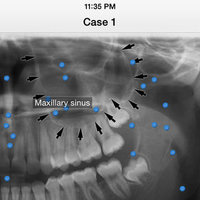

iPanoramic

Panoramic radiographs provide a quick overview of the patient’s teeth, jaws, and bone. This is useful for diagnoses and treatment planning.

The app provides dental students and dental hygiene an easy and fun way to master different anatomical landmarks. Dental practitioners can use the app to refresh their knowledge about panoramic radiographs. The app can be used a quick reference when needed. It's fully interactive and allows knowledge assessment through a quiz mode.